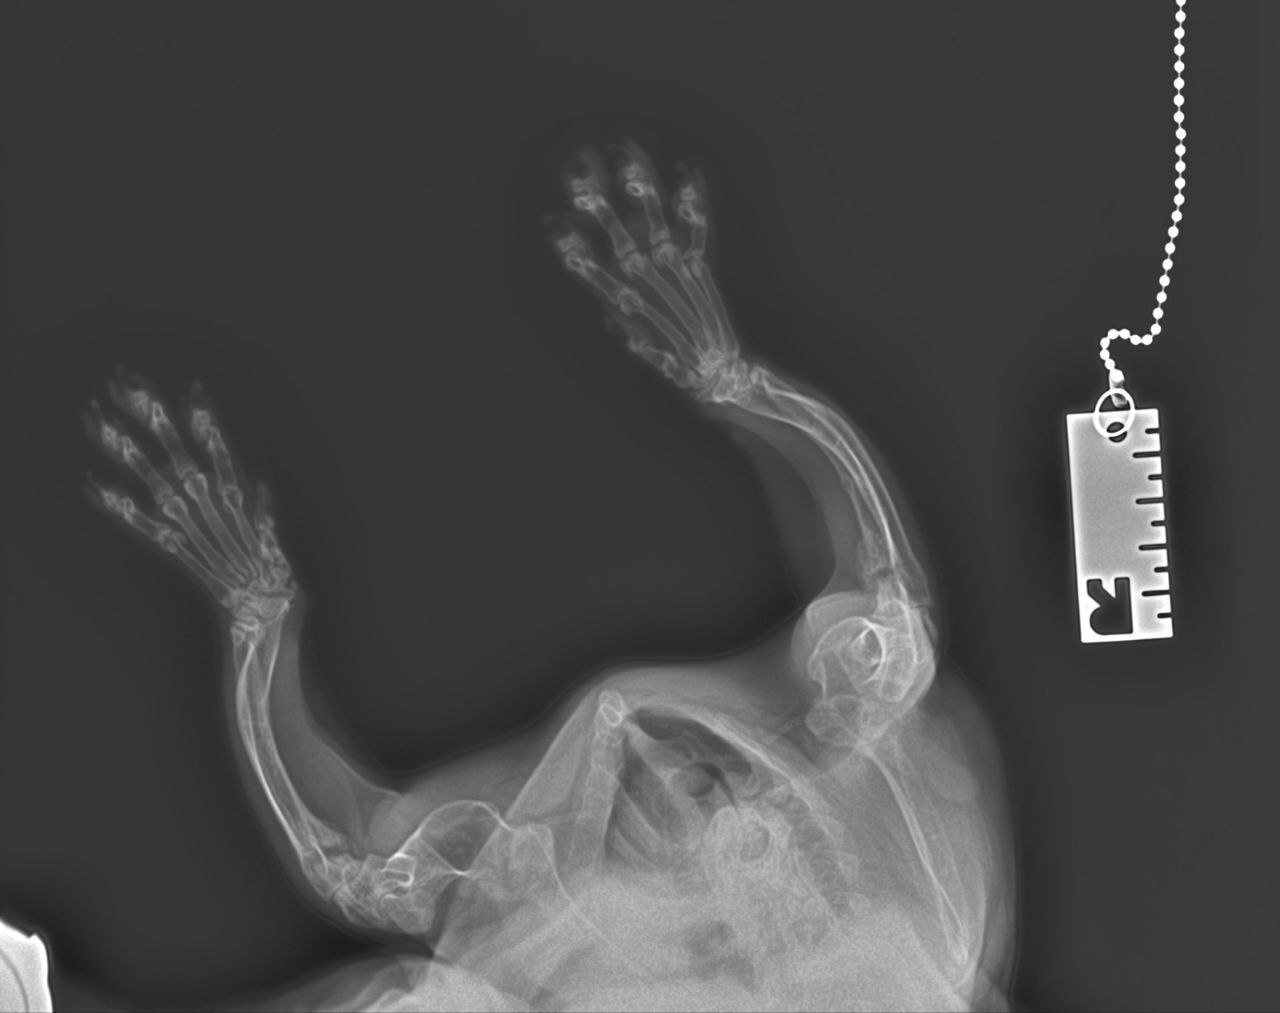

Наш пациент – кастрированный кот по кличке Порш, метис, изначально поступил в ноябре 2025 года на прием ортопеда-травматолога. У кота с рождения наблюдалась деформация костей скелета, хромота, непропорциональное укорочение конечностей, карликовость. Кроме того, владелицу беспокоило. Что кот малоподвижный, не активный, и большую часть времени – лежит в своей лежанке. Коту провели ортопедический осмотр и выполнили несколько рентгеновских снимков.

Наш ортопед-травматолог выделил основные изменения - признаки эпифизарной дискинезии (недоразвитие эпифизов длинных костей), укорочение тел позвонков в грудном отделе и задержка закрытия эпифизов.